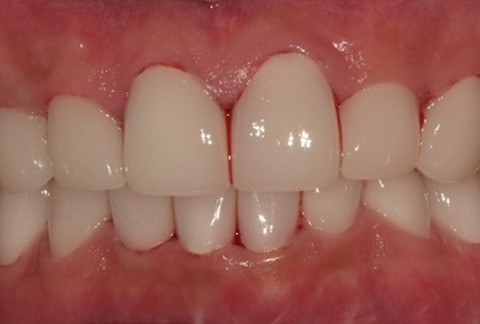

임플란트-보철-시-기성-어버트먼트가-아닌-맞춤-지대주-사용-보철-파절-위험-방지-음식물-끼임-방지-주위염-방지-맞춤-지대주는-환자의-구강환경에-맞는-교합을-구현할-수-있고-앞니-보철시-더욱-심미적으로-제작이-가능합니다

임플란트-전후사진